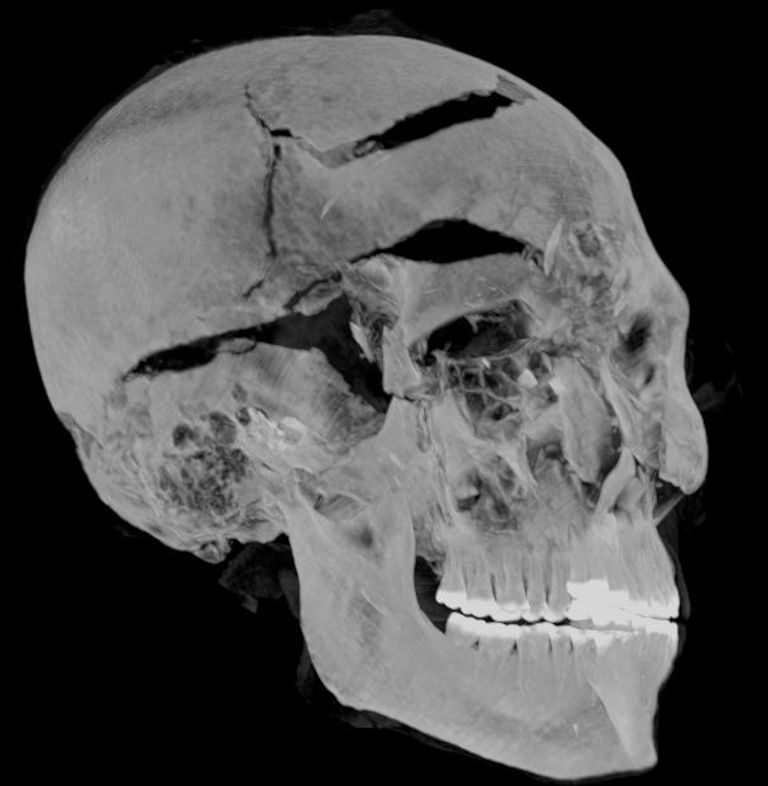

وقدم الباحثان المصريان زاهي حواس وسحر سليم، في بحثهما، تفسيرًا جديدًا للأحداث قبل وبعد وفاة الملك سقنن رع، استنادًا إلى صور الأشعة المقطعية ثنائية وثلاثية الأبعاد والتي تم تركيبها بواسطة تقنيات الكمبيوتر المتطورة، فيظهر تشوه الذراعين أنه يبدو أنه قد تم بالفعل أسر سقنن رع-تاعا الثاني في ساحة المعركة، وقيدت يديه خلف ظهره، مما منعه من صد الهجوم الشرس عن وجهه.

وكشف التصوير المقطعي لمومياء سقنن رع تاعا الثاني عن تفاصيل دقيقة لإصابات الرأس بما في ذلك جروح لم يتم اكتشافها في الفحوصات السابقة حيث أخفاها المحنطون بمهارة.

كما حددت دراسة التصوير المقطعي أن سقنن رع تاعا الثاني كان يبلغ من العمر قرابة الأربعين عامًا عند وفاته، بناءً على شكل العظام (مثل مفصل ارتفاق العانة) والذي تم الكشف عنه في الصور، ما يوفر التقدير الأكثر دقة حتى الآن.

وكشفت دراسة التصوير المقطعي المحوسب عن تفاصيل مهمة حول تحنيط جسد سقنن رع تاعا الثاني، على سبيل المثال، استخدم المحنطون طريقة متطورة لإخفاء جروح رأس الملك تحت طبقة من مادة التحنيط التي تعمل بشكل مشابه للحشوات المستخدمة في الجراحة التجميلية الحديثة، وهذا يعني أن التحنيط تم في ورشة تحنيط بالفعل وليس في مكان غير معد، كما تم تفسيره سابقًا.